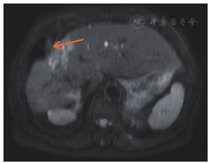

2012年7月起接受6次XELOX方案化疗,此后卡培他滨单药化疗1年;2013年7月影像学检查提示转移灶较前进展,肝脏出现新发转移灶;2013年9月16日针对肝转移瘤行射频消融术,2013年11月复查见肝Ⅷ段近膈顶处出现新病灶(图2)。2014年6月肺部CT未见明确转移灶,2014年11月右下肺考虑转移灶(图3)。2015年3月肺转移瘤较前进展,2015年3月起接受6个疗程FOLFIRI方案化疗(伊立替康150 mg/m2,ivgtt+氟尿嘧啶340 mg/m2,iv bolus+氟尿嘧啶2.2 g/m2,civ+亚叶酸钙330 mg/m2,ivgtt),2015年9月肝肺转移瘤均较前进展,2016年1月21日行肝转移瘤切除术,2016年2月胸部CT提示肺转移瘤进展,患者拒绝肺转移瘤介入治疗,2016年3月和4月行树突状细胞治疗。2017年3月肺CT:肺转移瘤增大,肝脏MRI肝Ⅷ段肿瘤存活(图4A),Ⅵ段新发转移癌(图4B)。2017年3月22日继续行FOLFIRI方案化疗,2017年4月—10月行10次西妥昔单抗+FOLFIRI方案化疗(伊立替康162 mg/m2,ivgtt+氟尿嘧啶365 mg/m2,iv bolus+氟尿嘧啶1.7 g/m2,civ+亚叶酸钙365 mg/m2,ivgtt+西妥昔单抗700 mg,ivgtt),2017年11月—2018年1月行5次西妥昔单抗单药(700 mg, ivgtt)靶向治疗,随访至2018年1月28日,生存时间超过94个月。